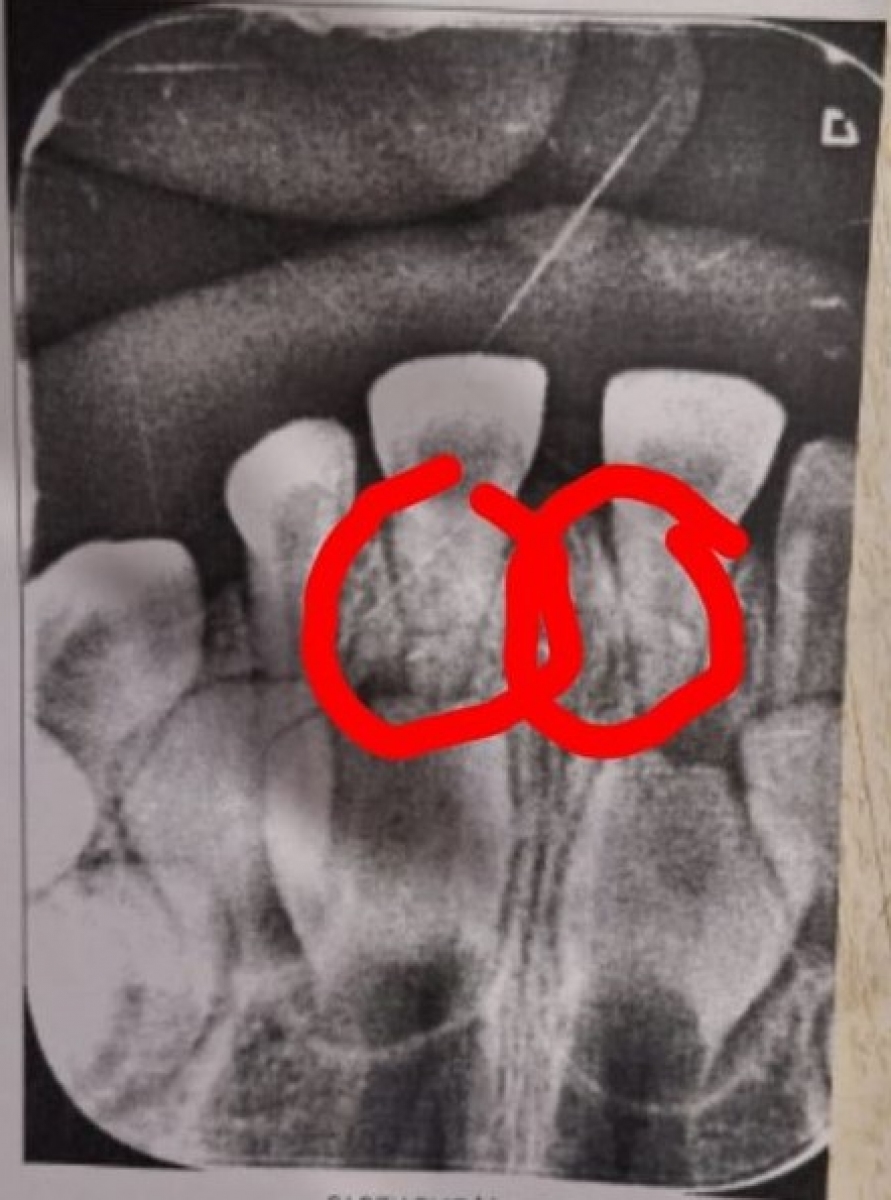

В последующие дни ребенок все время лежал - у нее болела голова, она не могла толком есть, передние зубы качались. В итоге, мама повела ее в стоматологию, где сделали снимки, результат оказался плачевный. Были переломаны корни двух передних зубов, так что их пришлось удалять. Теперь ребенок остался без передних зубов. Плюс ко всему получил сильную психологическую травму, так что пришлось наблюдаться у невролога, целый месяц ходили к психологу, потому что малышка напрочь отказывалась ходить в детсад. Девочка два месяца не посещала дошкольное учреждение, теперь шепелявит, врачи говорят, что травма скажется на прикусе, да и коренные зубы впоследствии будут расти кривые, потому что сломанные корни молочных зубов остались внутри.

Фото публикуется с согласия законных представителей несовершеннолетней.